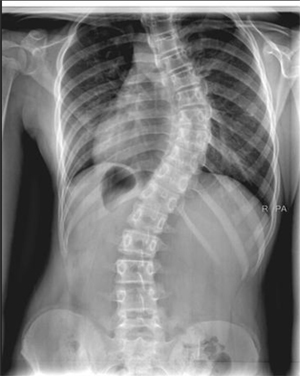

Omurgamızın yana eğilmeleriyle oluşan skolyoz, pek sık rastlanmasa da azımsanamayacak kadar mağduru olan bir omurga rahatsızlığıdır. Türkiye’de 2 milyonun üzerinde insanın sahip olduğu düşünülen bu rahatsızlığın genelde sebebi bilinmemekle beraber birkaç farklı nedeni bulunabilir.

Skolyoz doğuştan geliyor olabilir. Bu durumda gebelik döneminden kalan bir problem sonucu ortaya çıkar. Beyin felci sonucunda ya da kas ve sinir hastalıklarına bağlı da görülebilir. Genellikle normal gelişen bir omurgada, nedeni belli olmadan aniden baş gösterebilir. Bel ağrısı, sırttaki kozmetik kusurlar, gözle görülen bel eğiklikleri gibi belirtilerle kendisini gösterir

Skolyoz genelde ergenlik döneminde kendisini gösterse de çocuklar ve yetişkinlerde de bulunabilir. Ergenlik ve çocukluk dönemindeki skolyoz vakaları için, eğer eğrilik 20-25 ila 45 derece arasında ise skolyoz korse tedavisi tercih edilir. Skolyoz korse desteği yalnızca belirli eğrilik açıları için kullanılır. 45 dereceden fazla eğrilikler için genellikle ameliyat tedavisi uygulanır.

Skolyozun Dereceleri

Hafif skolyoz, omurlardaki eğriliğin 10 ila 20 derecenin arasında olduğu skolyoz tipidir. Genellikle tedavi gerektirmez ancak hasta olası bir ilerleme durumu için belirli aralıklarla muayene edilmelidir. Bu eğriliklerde skolyoza özgü egzersiler yapılabilir.

Orta derece skolyoz, eğriliğin 20 ila 45 derece arasında olduğu genelde çocuk ve ergenlerde kendisini hafif semptomlarla gösteren tiptir. Bu skolyoz tipinde cerrahi işlem tercih edilmez. Genelde iskelet gelişimi devam edene dek korse tedavisi uygulanır.

Şiddetli skolyoz, eğriliğin 45 derece ve üstü olduğu durumlarda kullanılan bir tabirdir.